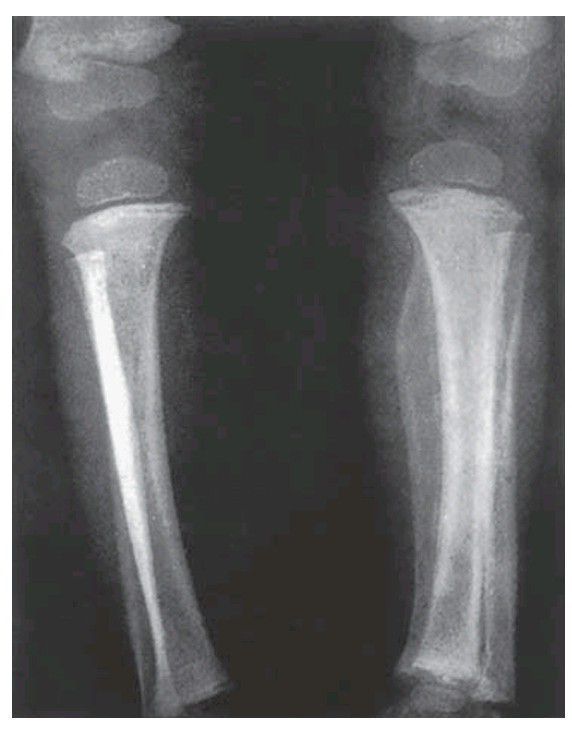

Scurvy. In contrast to rickets, calcifi cation is unimpeded and there is a thick layer of calcifi ed cartilage at the end of the bone. Osteoid formation, on the other hand, is poor, so that little bone can be formed. The attachment of the periosteum to the bone is weak, so that it is easily separated; haemorrhage beneath it (as here) is due to scorbutic purpura and this becomes calcifi ed.